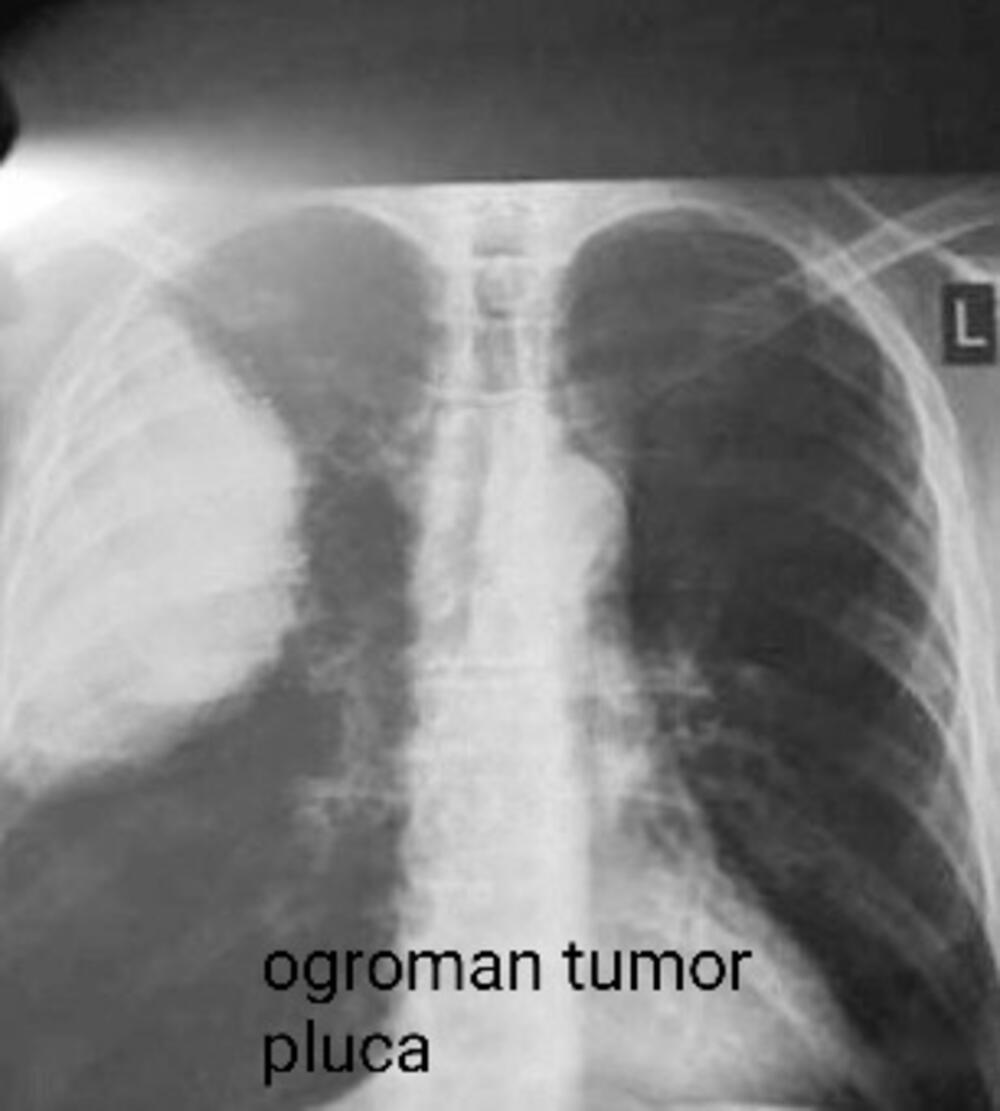

Još jedna od najčešćih bolesti u Srbiji je karcinom pluća koji je i najsmrtonosniji karcinom kod nas i u svetu.

- Prema statistici, Srbija zauzima drugo mesto u Evropi po smrtnosti, odmah posle Mađarske, a broj obolelih raste svake godine. Godišnje u Srbiji oboli 6.500 osoba, a nažalost, preko 4.600 izgubi bitku sa tom opakom bolešću. Po podacima Instituta za javno zdravlje Milan Jovanović Batut u Srbiji se svakodnevno dijagnostikuje 20 novih pacijenata, od kojih je sve više žena, a od ovog karcinoma umre 13 osoba. U svetu je, tokom 2020. godine, od karcinoma pluća obolelo oko 2,2 miliona ljudi od kojih je 1,8 miliona, nažalost, preminulo, navodi dr Slavica.

- Glavni faktor rizika za pojavu bolesti kod 90% muškaraca i 80% žena je pušenje, zatim genetski faktori i aerozagađenje. Zbog toga se pušačima posle 40. godine života, a i onima sa opterećujućom genetskom predispozicijom, savetuje da jednom godišnje urade snimak pluća. Za sve ostale, preporuka je jednom u dve godine, preventivno. Naravno, po potrebi i češće. Jedan od razloga za visoku smrtnost je kasno otkrivanje bolesti zbog nespecifičnih simptoma i nemogućnosti da se tumor otkrije u ranoj fazi zbog toga što nema dovoljno lekara niti dovoljno rendgen aparata za snimanje. Dijagnostiku je dodatno usporila pandemija korona virusa, pa je sada primetan veći broj pacijenata koji sa malignim oboljenjima dolaze u poodmakloj fazi, ističe naša sagovornica.

Ukoliko se otkrije u ranom stadijumu, uz primenu adekvatne terapije, sa karcinomom pluća može da se živi. Međutim, upravo je dijagnostika kamen spoticanja za pacijente koji imaju rak pluća.

- Pravovremenom operacijom nekih oblika tumora pluća i redovnim praćenjem može se postići potpuno izlečenje. Ako se otkrije kasno, smrtnost je vrlo visoka. Ova maligna bolest pluća može biti asimptomatska dugo vremena, čak i nekoliko godina, tako da je veliki problem što se ne otkriva na vreme, kao što je to slučaj kod drugih vrsta tumora koji daju rane simptome i za koje postoje jasni programi skrininga (karcinom dojke, grlića materice ili debelog creva), navodi doktorka Plavšić.